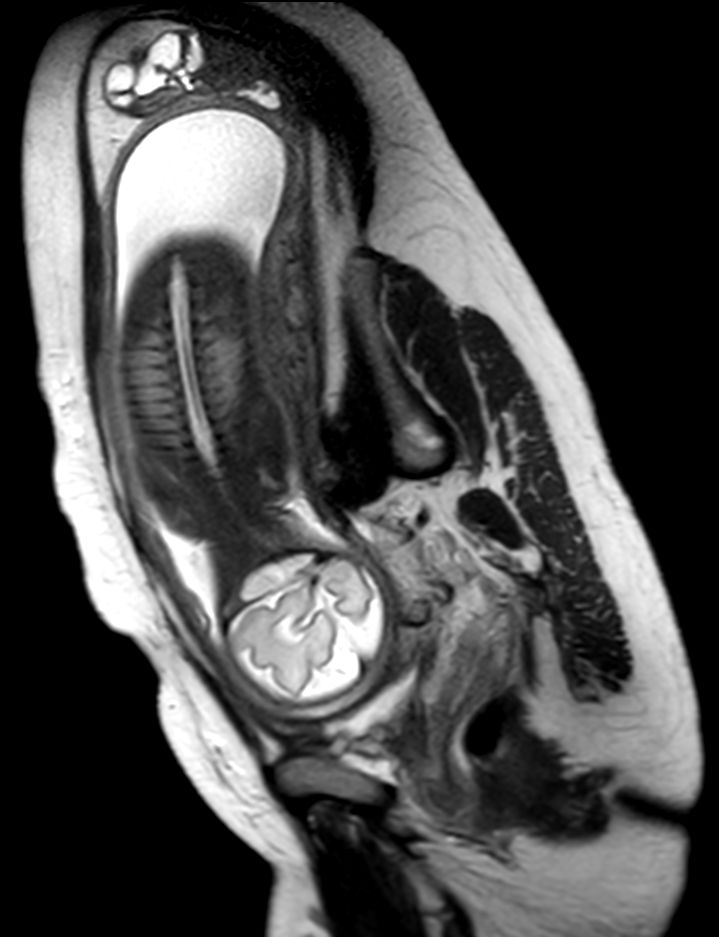

Pregnant patient, referred to MRI for fetal brain imaging because of suspected arachnoid cyst.

Sagittal T2w TSE single shot (Spine)